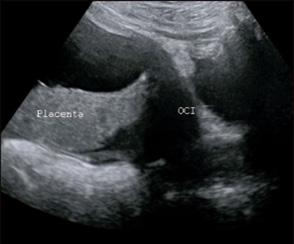

Figura 11. Ecografía de I trimestre Examen de certeza para confirmar un embarazo eutópico y viable

En la del I trimestre (10-14 semanas), se confirman la gestación, la edad gestacional de forma más precisa midiendo la longitud craneocaudal (LCC)

(ENAM EXTRA 2021), y la vitalidad del embrión (actividad cardiaca) (ENAM EXTRA 2020)

Es considerada la ecografía más importante por 3 propósitos:

Evaluación de riesgo genético (riesgo de cromosomopatías o aneuploidías)

Evaluación morfológica (exclusión de malformaciones visibles en el 1er trimestre)

Evaluación de riesgo de preeclampsia y RCIU.